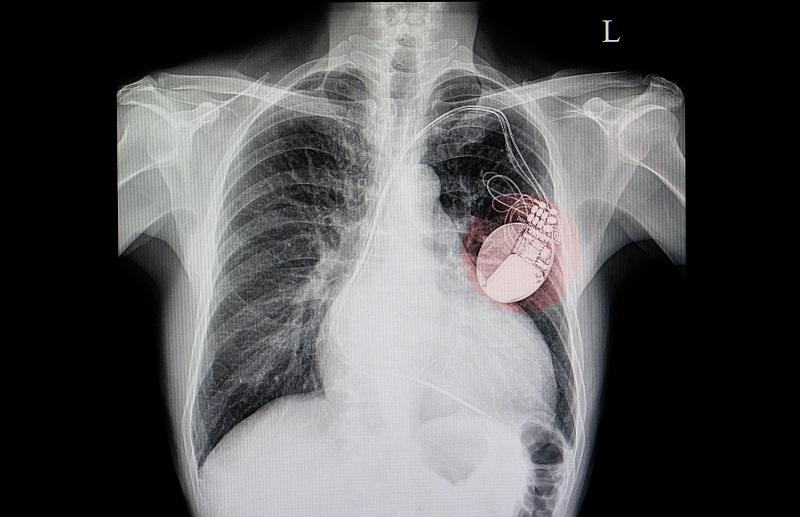

Történelmi engedélyt adott ki az Európai Unió. A Carmat nevű francia orvostechnológiai cég ugyanis 2020 decemberében megkapta az Európai Gazdasági Térségben értékesített termékek megfelelőségét jelző CE jelölést az általa fejlesztett teljesen mesterséges szívre (TAH) – adta hírül iflscience.com portál. Ez azt jelenti, hogy olyan műszív kerülhet értékesítésre, amelyet legalább átmenetileg megkaphatnak szívátültetésre váró betegek. Az akkumulátora akár négy óráig is bírja egy töltéssel, így több korábbi próbálkozással ellentétben a páciens nincs ágyhoz kötve.

Az engedély egyelőre csak olyan esetekre terjed ki, amelyekben a páciens olyan súlyos kétkamrás szívelégtelenségben szenved, hogy semmilyen kórházi kezeléssel nem gyógyítható, és az eszköz beültetését követő 180 napon belül várhatóan valódi szívet kap. Ugyanakkor a Carmat állítása szerint a műszív akár 5 évig is működhet, ami 230 millió szívverést jelent. A cég januárban megkezdi a gyártási kapacitásának bővítését, valamint felveszi a kapcsolatot a potenciális vásárlónak tartott klinikákkal.